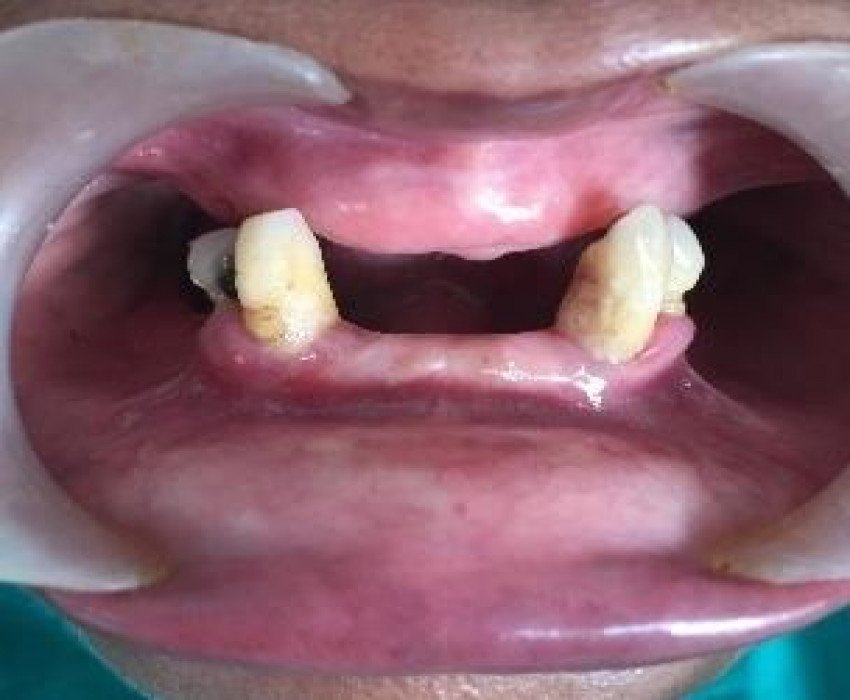

Patient reported to the Dept. of prosthodontics at Saraswati Dental College & Hospital with a chief complaint of replacement of missing teeth due to inability to chew properly. As retention is always a challenge in the fabrication of lower denture. After complete clinical & radiographic evaluation we have proposed mandibular bar supported overdenture & maxillary conventional complete denture to the patient. After obtaining patient consent, Dolder Bar precision attachment overdenture delivered to the patient to improve the retention of the lower denture as well as improve proprioception by preserving the existing teeth. Patient was highly satisfied with the esthetic and retention of both the denture.